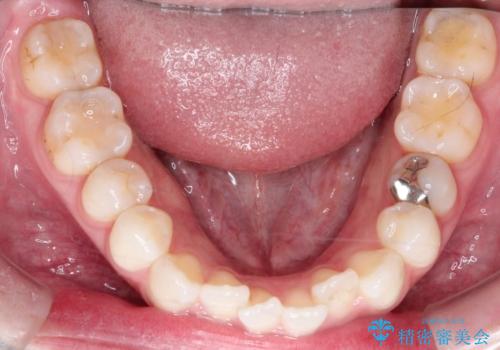

【インビザライン】がたつきをなおしたい

- 上下の前歯の凸凹が気になり、来院されました。

インビザラインで綺麗に仕上がり、満足していただきました。